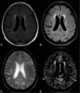

Subacute cephalohematoma

T1-hyperintense extracranial mass